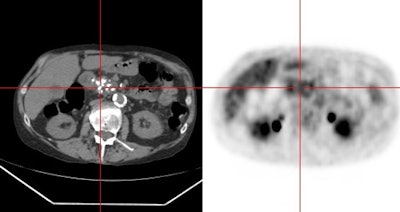

|

Chronic pancreatitis: The patient below underwent PET imaging for evaluation of a left upper lung nodule. Incidental note was made of diffuse pancreatic tracer accumulation (cross hair and black arrows). Coregistered CT imaging revealed findings consistent with chronic pancreatitis. |